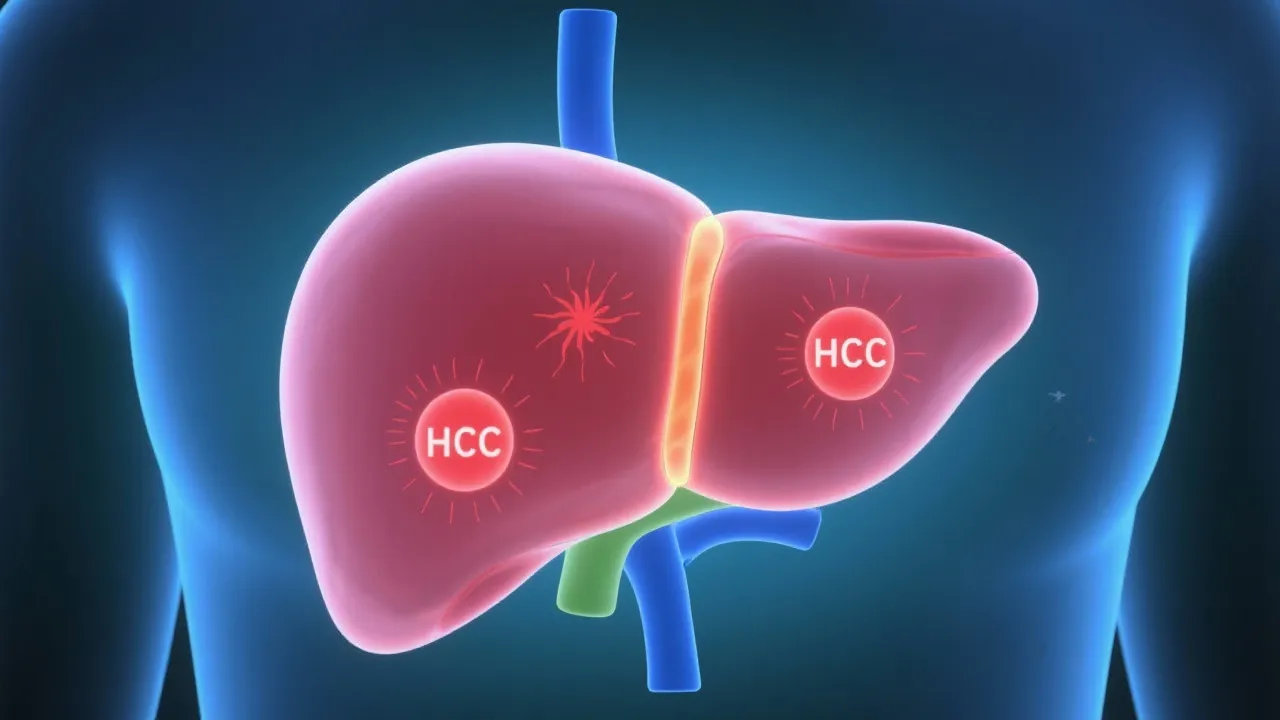

Non-Alcoholic Fatty Liver Disease (NAFLD) and its progression to Hepatocellular Carcinoma (HCC) pose significant health challenges worldwide. This article explores the relationship between NAFLD and HCC, providing an objective analysis of the risk factors and potential preventive measures for individuals suffering from fatty liver disease.

Non-Alcoholic Fatty Liver Disease (NAFLD) is increasingly recognized as a major public health issue. With its prevalence growing, an understanding of its potential progression to Hepatocellular Carcinoma (HCC) is crucial for effective management and prevention strategies. NAFLD encompasses a spectrum of liver conditions ranging from simple steatosis to non-alcoholic steatohepatitis (NASH), which can eventually lead to cirrhosis and HCC. The rising incidence of NAFLD and its complications underscores the need for comprehensive research and targeted interventions.

NAFLD-related HCC has become a focal point for researchers and healthcare professionals alike. The link between NAFLD and HCC lies in the gradual liver damage induced by fat accumulation, inflammation, and fibrosis. The liver can tolerate fat accumulation for some time; however, the transformation into NASH represents a critical point when inflammation and damage ensue. Unlike alcoholic liver disease, NAFLD progresses without the influence of alcohol, making lifestyle choices, dietary habits, and genetic factors significant contributors to disease onset and progression.

In recent years, studies have shown that the presence of hepatic steatosis itself is a strong predictor of liver-related morbidity. As steatosis progresses to NASH, the risk of cirrhosis increases considerably. Once cirrhosis develops, there is a significantly heightened risk of HCC. It is estimated that 5% to 15% of patients with NASH may progress to cirrhosis, and approximately 5% to 10% of those with cirrhosis will develop HCC. This progression is concerning, highlighting the need for early detection and intervention strategies to stem this tide.